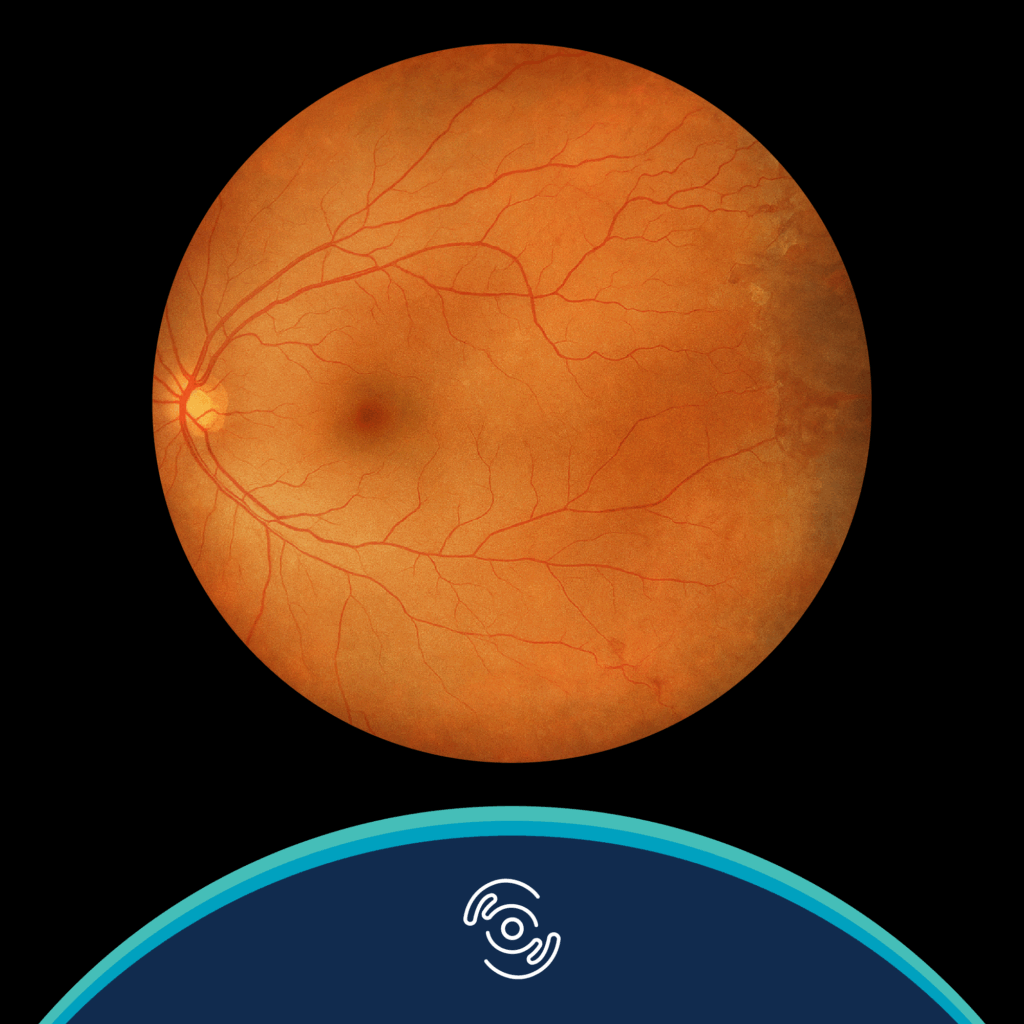

Phillpotts, BA, Duong, HV. Retinopathy, Hemoglobinopathies. Medscape Reference. Updated: 14 December 2021. Available at: